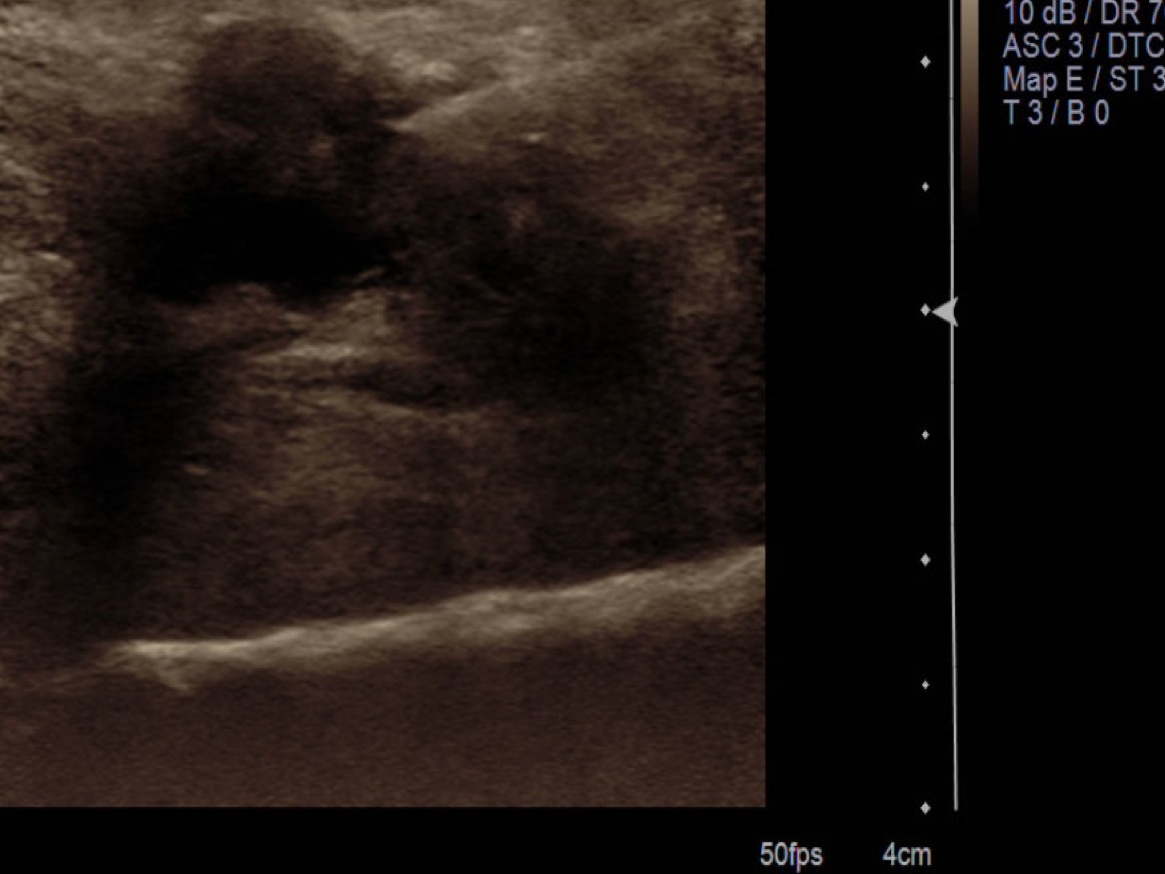

3. Pre-procedure scanning looking from either plantar or dorsal looking for Morton’s neuroma in the webspaces. Place probe in long axis along the distal metatarsals. If well visualized from the dorsal aspect, prefer to place ultrasound probe in that position. Sometimes, it is preferred to have the patient dorsiflex and have the probe plantar, particularly when the patient has subluxations of the MTP joints.